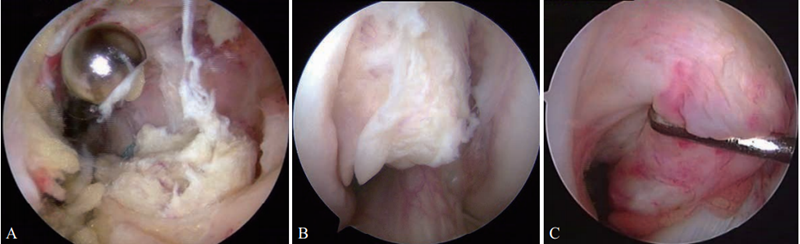

1.关节镜下探查

首先在关节镜下探查确定PCL断裂情况(图1)。单束重建是多数学者最常用的手术。取腘绳肌腱编制成4股移植物,探查时尽量保留PCL残端。

图1 关节镜下PCL断裂情况

A.PCL从胫骨止点断裂;B. PCL从股骨止点断裂;C. PCL断裂后松弛失去张力